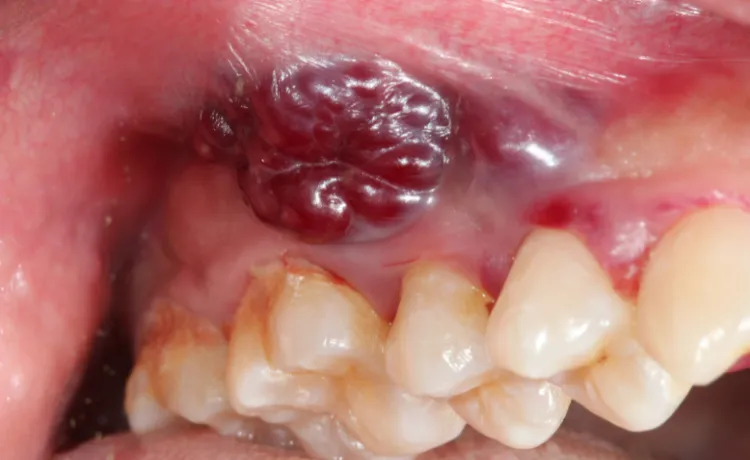

Guzek, zgrubienie, narośl: jak odróżnić je od aft i innych niegroźnych zmian?

Wyczuwalne zmiany, takie jak guzki, zgrubienia czy narośle, mogą pojawić się na języku, wardze, dziąśle lub wewnątrz policzka. Czasem są to również nacieki, czyli stwardnienia tkanki, które mogą ograniczać ruchomość języka. Kluczowe jest odróżnienie ich od aft, które zazwyczaj są bardzo bolesne i goją się w ciągu maksymalnie dwóch tygodni. Zmiany nowotworowe mogą być początkowo bezbolesne, a ich twardość i utrzymywanie się przez dłuższy czas to powód do niepokoju.

Zmiany koloru błony śluzowej, takie jak wspomniane już białe i czerwone plamy, są najważniejsze. Jednak inne nietypowe odcienie, na przykład ciemniejsze przebarwienia, które towarzyszą naciekom, również powinny zwrócić naszą uwagę. Ważne jest, aby pamiętać, że nie każda zmiana koloru oznacza raka. Jednakże, jeśli zauważysz jakąkolwiek nieustępującą zmianę w kolorze lub fakturze błony śluzowej, która utrzymuje się dłużej niż dwa tygodnie, zawsze warto skonsultować to z lekarzem. Lepiej dmuchać na zimne.

Język jest najczęstszą lokalizacją raka jamy ustnej, szczególnie jego brzegi i spód. Objawy, na które należy zwrócić uwagę, to przede wszystkim niegojące się owrzodzenia, guzki lub nacieki, które mogą powodować ból, trudności w poruszaniu językiem, a nawet utrudniać mówienie i połykanie. Często zmiany te są twarde w dotyku i mogą być początkowo bezbolesne, co niestety opóźnia diagnozę.

Dno jamy ustnej, czyli obszar pod językiem, oraz wewnętrzna strona policzków to kolejne miejsca, gdzie rak jamy ustnej często się rozwija. W tych rejonach należy szukać białych lub czerwonych plam (leukoplakii, erytroplakii), a także wszelkich zgrubień czy owrzodzeń. Ze względu na ukryte położenie, zmiany w tych miejscach mogą być trudniejsze do zauważenia podczas rutynowego samobadania, dlatego tak ważne jest dokładne oglądanie całej jamy ustnej.